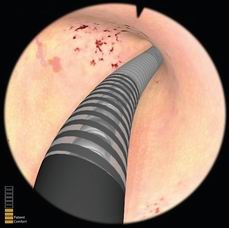

宫腔镜手术模拟器用来模拟临床宫腔镜手术,培训医师宫腔镜手术标准操作。系统可模拟宫腔镜在子宫内的进出、液体流量的控制、镜头的调节、镜头的旋转、器械的旋转、环形电极的使用等等。系统可模拟正常组织、病理组织、软组织损伤等。操作不当可引起出血、液体压力过高等并发症。操作时有力反馈手术手感,可对操作过程评估、打分。

可进行正常、异常子宫的各项检查,让学员在安全的环境中学习、掌握冲水、控制内镜检查整个宫腔等基本操作